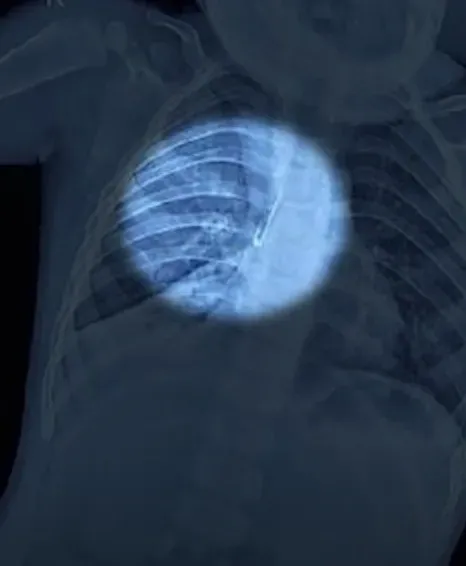

खांसी बढ़ी तो खुला राज, एक्सरे में दिखी अजीब वस्तु

दमोह जिले के हीरा सिंह की बेटी गरिमा को एक सप्ताह से लगातार खांसी हो रही थी। परिवार ने पहले उसे निजी अस्पताल में दिखाया, लेकिन कोई सुधार नहीं हुआ। एक्सरे कराने पर डॉक्टरों को फेफड़े में किसी अजीब वस्तु के फंसे होने का शक हुआ। तुरंत गरिमा को जबलपुर मेडिकल कॉलेज रेफर कर दिया गया।

26 अक्टूबर की रात बच्ची को मेडिकल कॉलेज के बाल रोग विभाग में भर्ती किया गया। ईएनटी विभाग की टीम ने जांच में पाया कि दाहिने फेफड़े की मुख्य श्वसन नली में एलईडी लाइट फंसी है। इतनी छोटी बच्ची पर ऑपरेशन बेहद जोखिम भरा था, लेकिन डॉक्टरों ने तुरंत ब्रोंकोस्कॉपी की और लाइट को सफलतापूर्वक निकाल लिया। डॉक्टरों के मुताबिक, थोड़ी सी देरी भी जानलेवा साबित हो सकती थी।